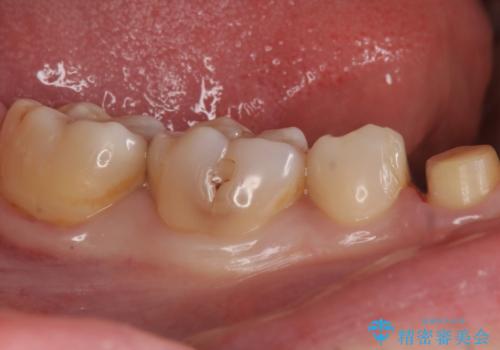

残った歯が薄い状態で保存するとその後の破折リスクが高くなります。

予防的に歯を削りクラウンにすることで治療後の破折リスクを減らすことができます。